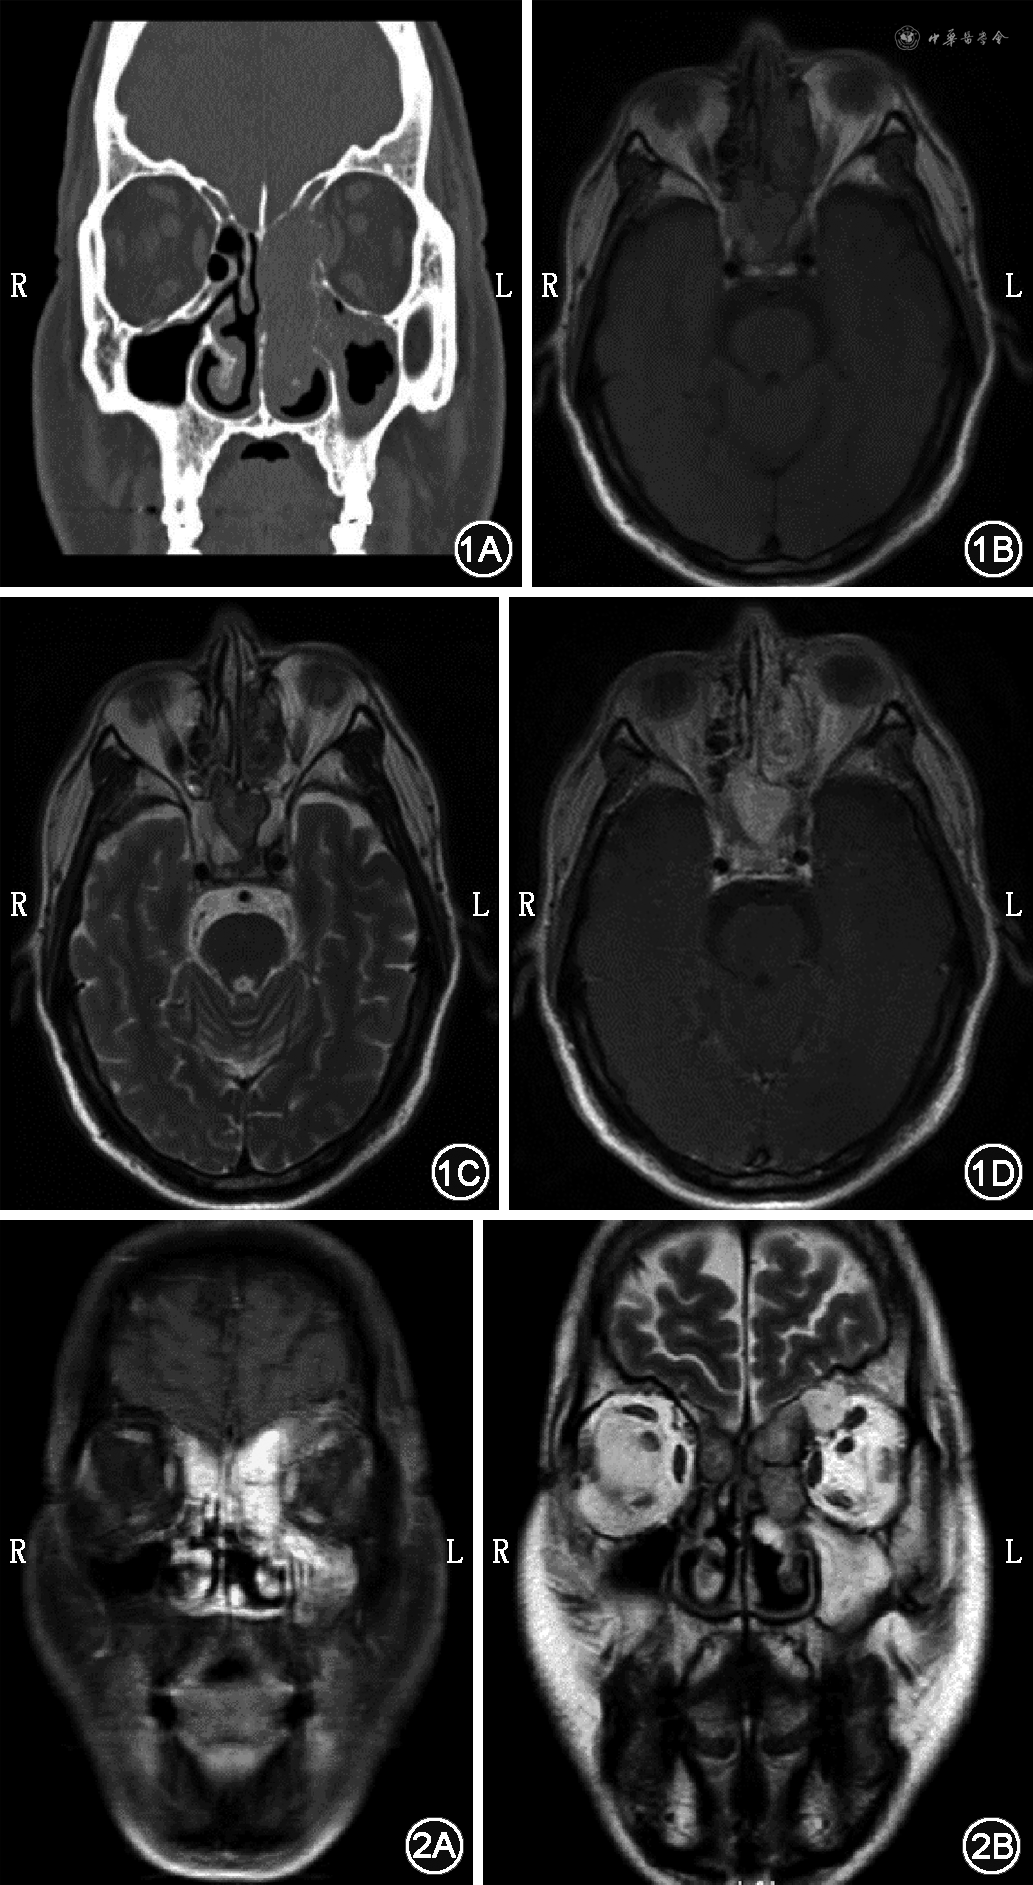

例3 患者男,50岁,因右眼复视2个月、加重3 d就诊。患者曾于4年前因肾癌行左肾摘除术。专科体格检查:右眼复视,粗测无明显视力下降,眼球外展障碍,眼睑略下垂,鼻中隔前份明显右偏,右侧蝶筛隐窝处略膨隆。颅底CT示蝶窦区团块状软组织影,大小约38 mm×37 mm×26 mm,蝶窦、蝶骨、蝶鞍、枕骨部分骨质破坏(图4A)。MRI示蝶窦区团块状稍长T1等T2信号影,内见斑片状短T1信号,大小约44 mm×32 mm×26 mm(图4B、C)。全身麻醉下行手术探查,见肿瘤占据蝶窦,且向下沿斜坡前方突至枕骨大孔,切除斜坡前方肿物,见斜坡旁颈内动脉段骨质部分缺损,斜坡偏右侧近海绵窦下方部分骨质破坏,肿物压迫右侧外展神经,并侵及左侧海绵窦下方斜坡旁骨质。完全切除肿物,电钻磨除受侵骨质后,见部分硬脑膜暴露,取左侧鼻中隔游离黏膜瓣修补。术后病理回报支持肾透明细胞癌转移。免疫组化染色结果:CK(AE1/AE3)少量(+)、Vimentin(+)、CD10(+)、PAX-8(+)、CAIX少量细胞膜(+)、p63(-)、S-100(-)、CgA(-)、Syn(-)、CK7(-)、HMB45(-)、Ki67(阳性率10%)、P504s(+)、TFE3(+)、EMA(-)、CD117(-)、MelanA(-)。